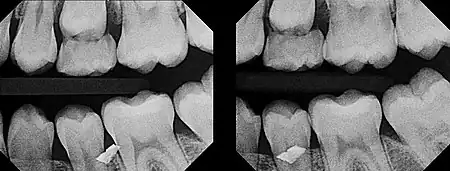

In 1909, Charles A. Clark described a radiographic procedure for localizing impacted teeth to determining their relative antero-posterior position.[1] If the two teeth (or, by extension, any two objects, such as a tooth and a foreign object) are located in front of one another relative to the x-ray beam, they will appear superimposed on one another on a dental radiograph, but it will be impossible to know which one is in front of the other. To determine which is in front and which is behind, Clark proposed his SLOB rule, as a complicated set of three radiographs, but which can be simplified as follows using just two:

- Expose another film while angle of the x-ray beam has been changed. If an object moves in the same direction as the source of the x-ray beam, it is lingual to the other object. If the object moves in the opposite direction of the source, it is buccal to the other object.

- Same Lingual; Opposite Buccal

In 1952, Richards amended this rule using only 2 radiographs,[2][3] asserting that the object positioned more buccally will move more relative to the object positioned more palatally or lingually.

As a generalization, but not specifically stated as part of Richards' buccal object rule, the more buccal an object is (i.e. the closer it is to the x-ray source) the more it will move in the second radiograph when repositioning the x-ray source.